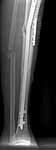

A> Some feedback regarding the case discussed here 6 month ago

I attached images with the nail (Dec 2003) and today with the broken

plate. The fracture site is pretty mobile.

We plan to remove the plate and perform closed nailng.